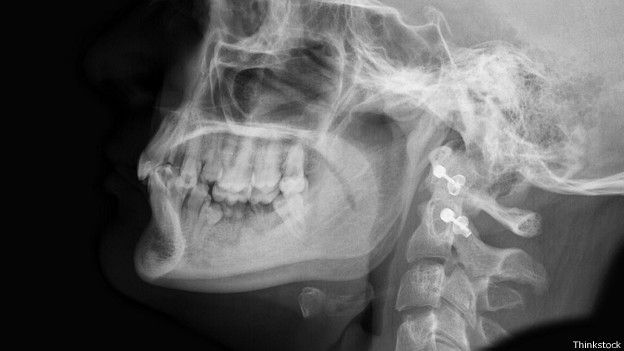

Image copyrightThinkstockImage captionNi siquiera nuestros parientes extintos contaban con un mentón.

Incluso los neandertales, nuestros parientes extintos, carecían de ella.

De hecho, una de las formas en que los científicos pueden diferenciar un cráneo de humano moderno de un neandertal es por el mentón (o su ausencia).